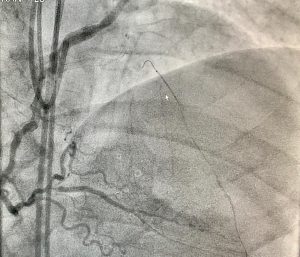

São poucos Centros no Japão e no mundo que realizam esse tipo procedimento, sendo considerado raro e caro.

O paciente veio referenciado pelo Japão, sendo atendido pela equipe da Hemodinâmica, do HC I, a qual realizou o procedimento em referência. O paciente teve já alta e passa bem.

“A capacidade e a qualidade dos serviços prestados pela Hemodinâmica do HCFAMEMA, não se resume apenas na realização desse procedimento, mas sim de um conjunto de técnicas aplicadas pelo Serviço no atendimento à população assistida, beneficiando principalmente os pacientes do SUS,” ressaltou o Prof. Dr. Igor Ribeiro de Castro Bienert, médico da Hemodinâmica do HCFAMEMA.

“O HCFAMEMA apoia e incentiva incorporação de novas tecnologias para melhoria da qualidade da assistência a saúde da nossa população. E esse procedimento que foi realizado é complexo, procedido em casos extremos, em centros altamente especializados no mundo e põe o HCFAMEMA ao lado de grandes instituições internacionais “, enfatizou a Superintendente do HCFAMEMA, Dra. Paloma Aparecida Libanio Nunes.